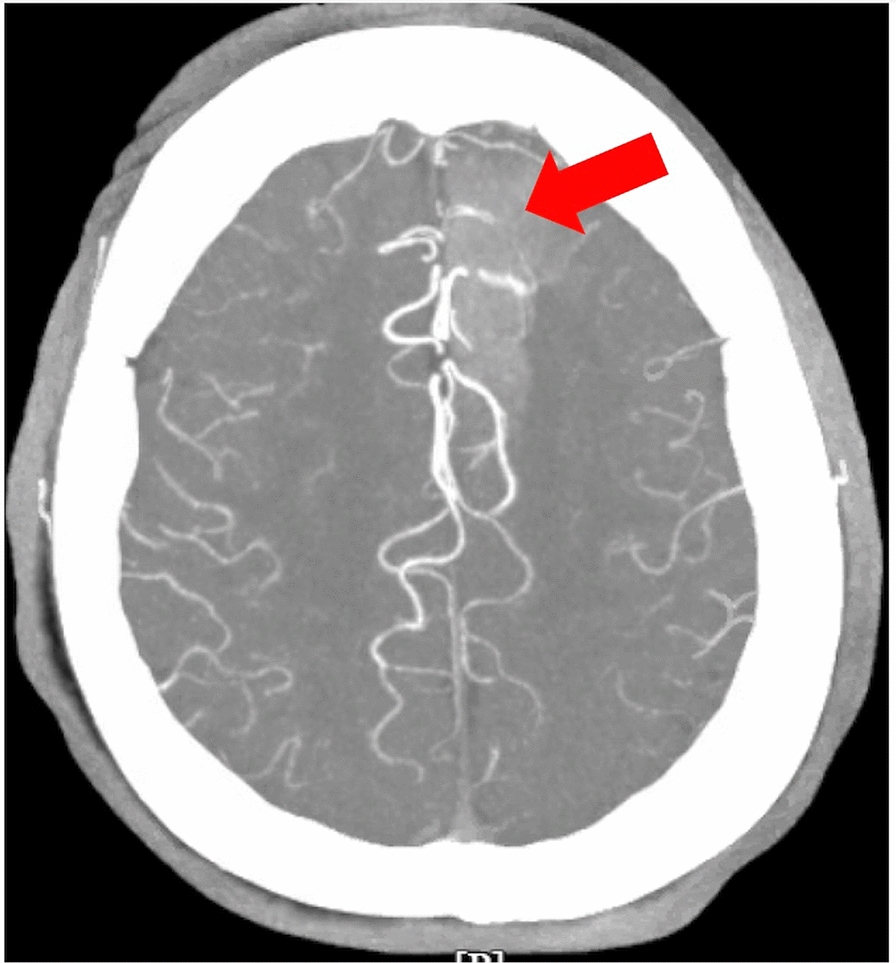

Case presentation: We report a case of a 68-year-old Hispanic woman with diabetes, hypertension, dyslipidemia, and hypopituitarism secondary to Sheehan syndrome, who presented with new-onset seizures after abruptly discontinuing chronic steroid therapy. Her symptoms included progressive weakness and behavioral changes over several weeks. Initial evaluation revealed hyperglycemia, mild hyponatremia, and no hyperkalemia-findings consistent with secondary adrenal insufficiency-associated seizures, although contributing to initial diagnostic uncertainty. Brain imaging incidentally identified a developmental cerebral venous anomaly, which was initially suspected as a potential cause of the seizures. In addition, echocardiographic findings were consistent with Takotsubo cardiomyopathy, likely precipitated by the stress of her medical condition. However, further evaluation confirmed adrenal insufficiency with low cortisol and adrenocorticotropic hormone levels, and subnormal response to cosyntropin stimulation. Management included hydrocortisone for adrenal insufficiency and levetiracetam for seizure prophylaxis, leading to symptom resolution and no recurrence of seizures.